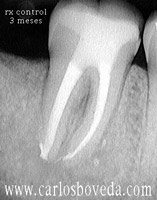

Video de un Retratamiento de Conductos en Una Sesión - (formato Quicktime)